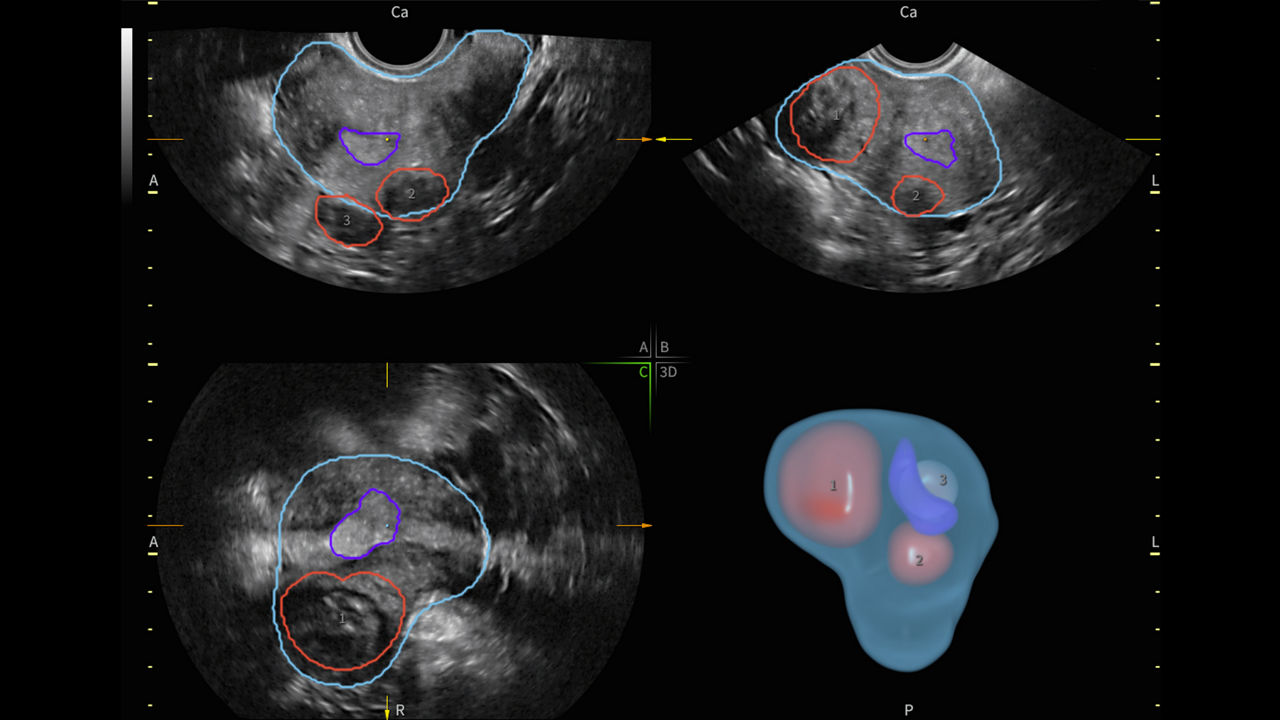

88%

Segment fibroids with 88% accuracy using Fibroid Mapping